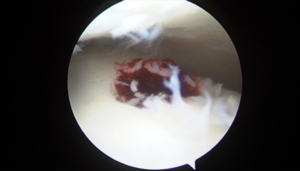

Description:

A layer of cartilage covers the bones where they meet in the joints, acting as a cushion to allow smooth movement. Osteochondral lesions occur when an area of this cartilage lining is damaged. They can cause pain, clicking, locking, grinding and giving way in the ankle joint.

Treatment:

Mild lesions will likely heal with physiotherapy. More severe lesions may necessitate keyhole surgery.

Our research:

The treatment of osteochondral lesions has been the topic of a review chapter edited by an international foot and ankle society that I was commissioned to author. Link to review chapter